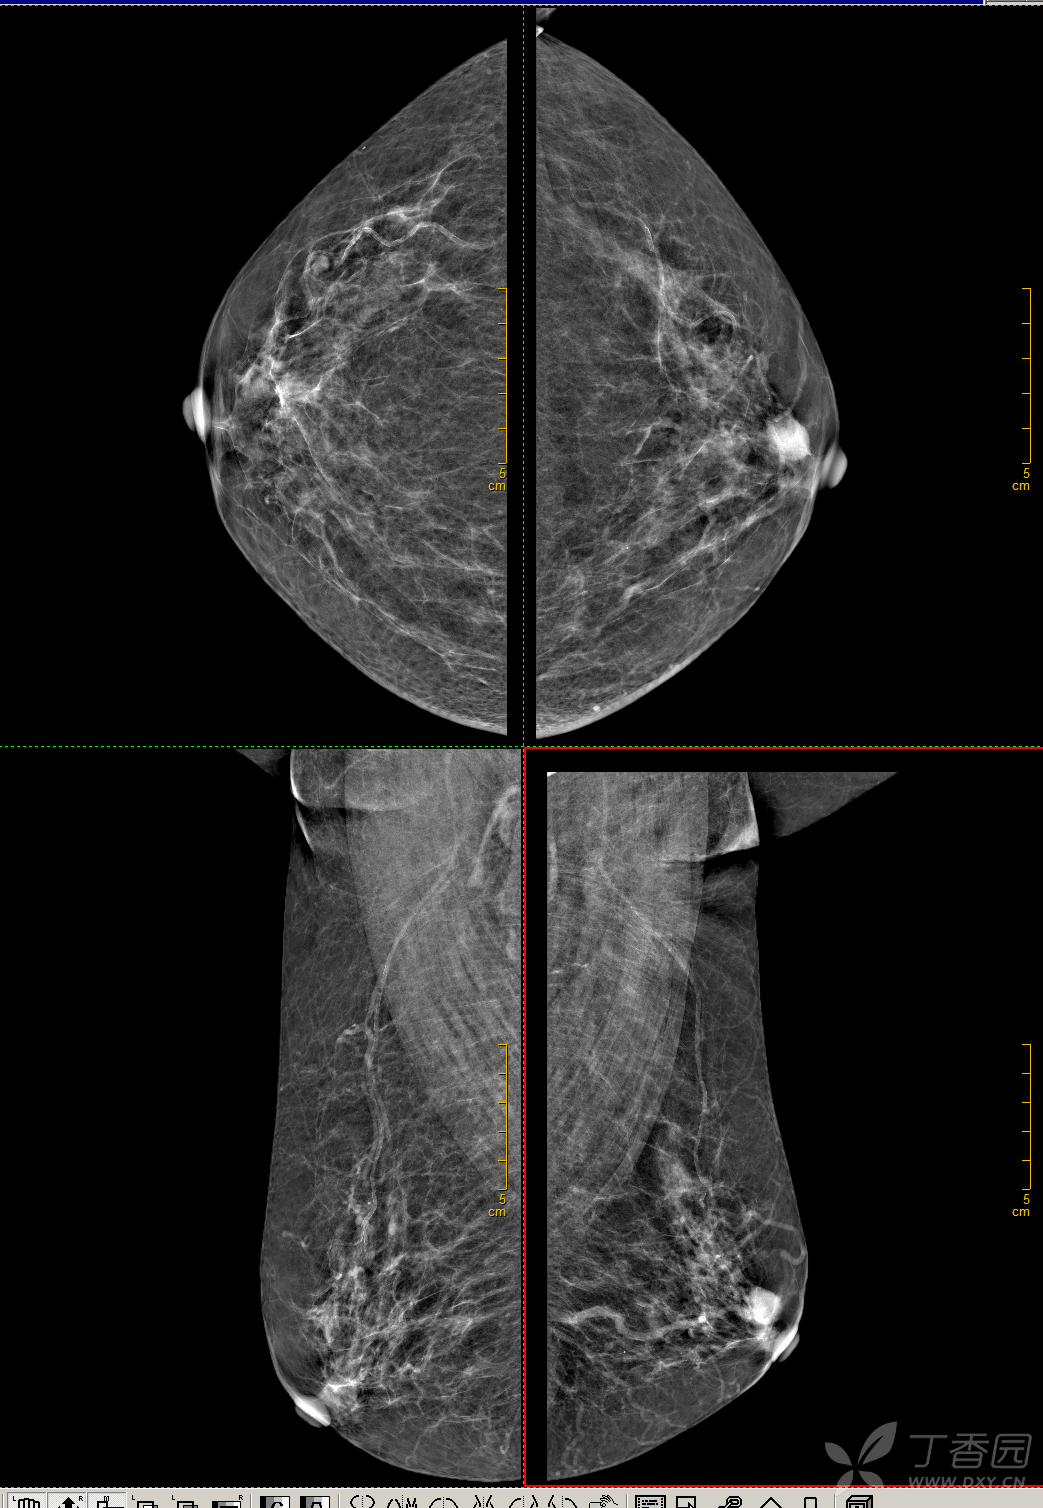

患者乳腺钼靶头足位射片示:左乳不规则肿物.

【读片】45岁,左乳上方肿块(有病理) [病例帖]

左乳外上肿块为浸润性导管癌,钼靶所示钙化灶为导管原位癌,钼靶mlo位

(17) 写美篇 病灶局部放大图像,左乳外上象限可见椭圆形高密度肿块影